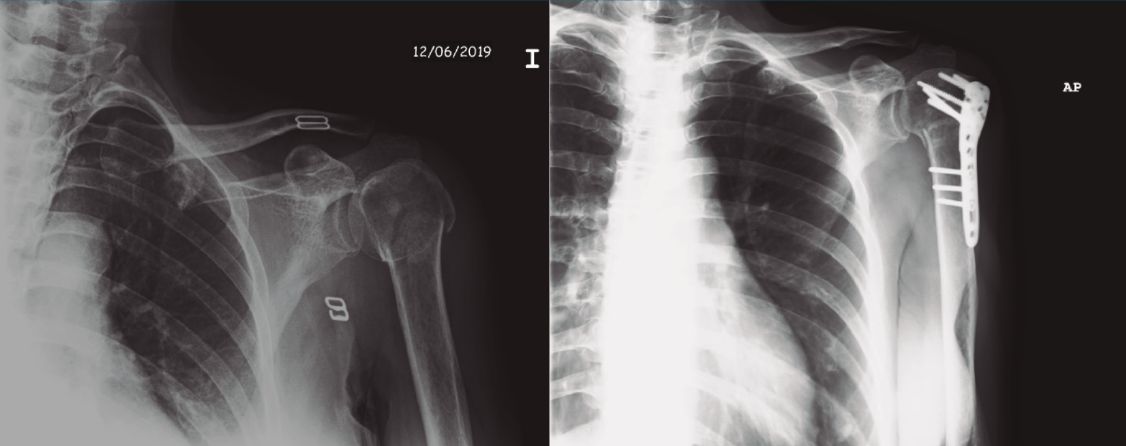

Protocolo rehabilitador en fracturas de húmero proximal quirúrgicas: osteosíntesis (Figura 8)

Figura 8. Radiografía de una fractura de húmero pre- y postosteosíntesis.

La RHB postoperatoria difiere según la clasificación de la fractura o según el sistema de osteosíntesis. En la revisión de la literatura realizada por Rosen et al.(4), no se obtuvieron conclusiones, aunque el tema fue muy poco discutido.

El protocolo que proponemos es básicamente el mismo que el descrito en las PHF no quirúrgicas, con las excepciones y consideraciones que se detallan a continuación (Tabla 1):